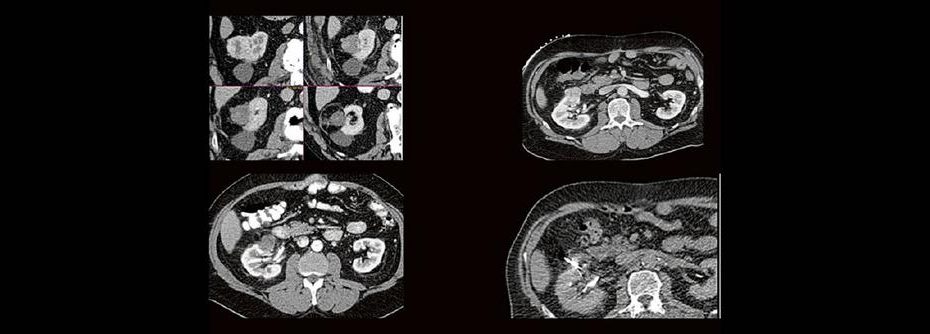

Back to the roots! Gute Kenntnisse der Anatomie sind der Schlüssel zur guten Planung, Durchführung und richtigen Diagnosestellung im CT des Abdomens. Lernen sie unverkrampft

- richtiges Kontrastmittel-Timing im Bild erkennen

- Anatomie in Pathologie übersetzen

Haben Sie es erkannt? Probieren Sie selbst im lockeren Fallquiz zum mitraten.